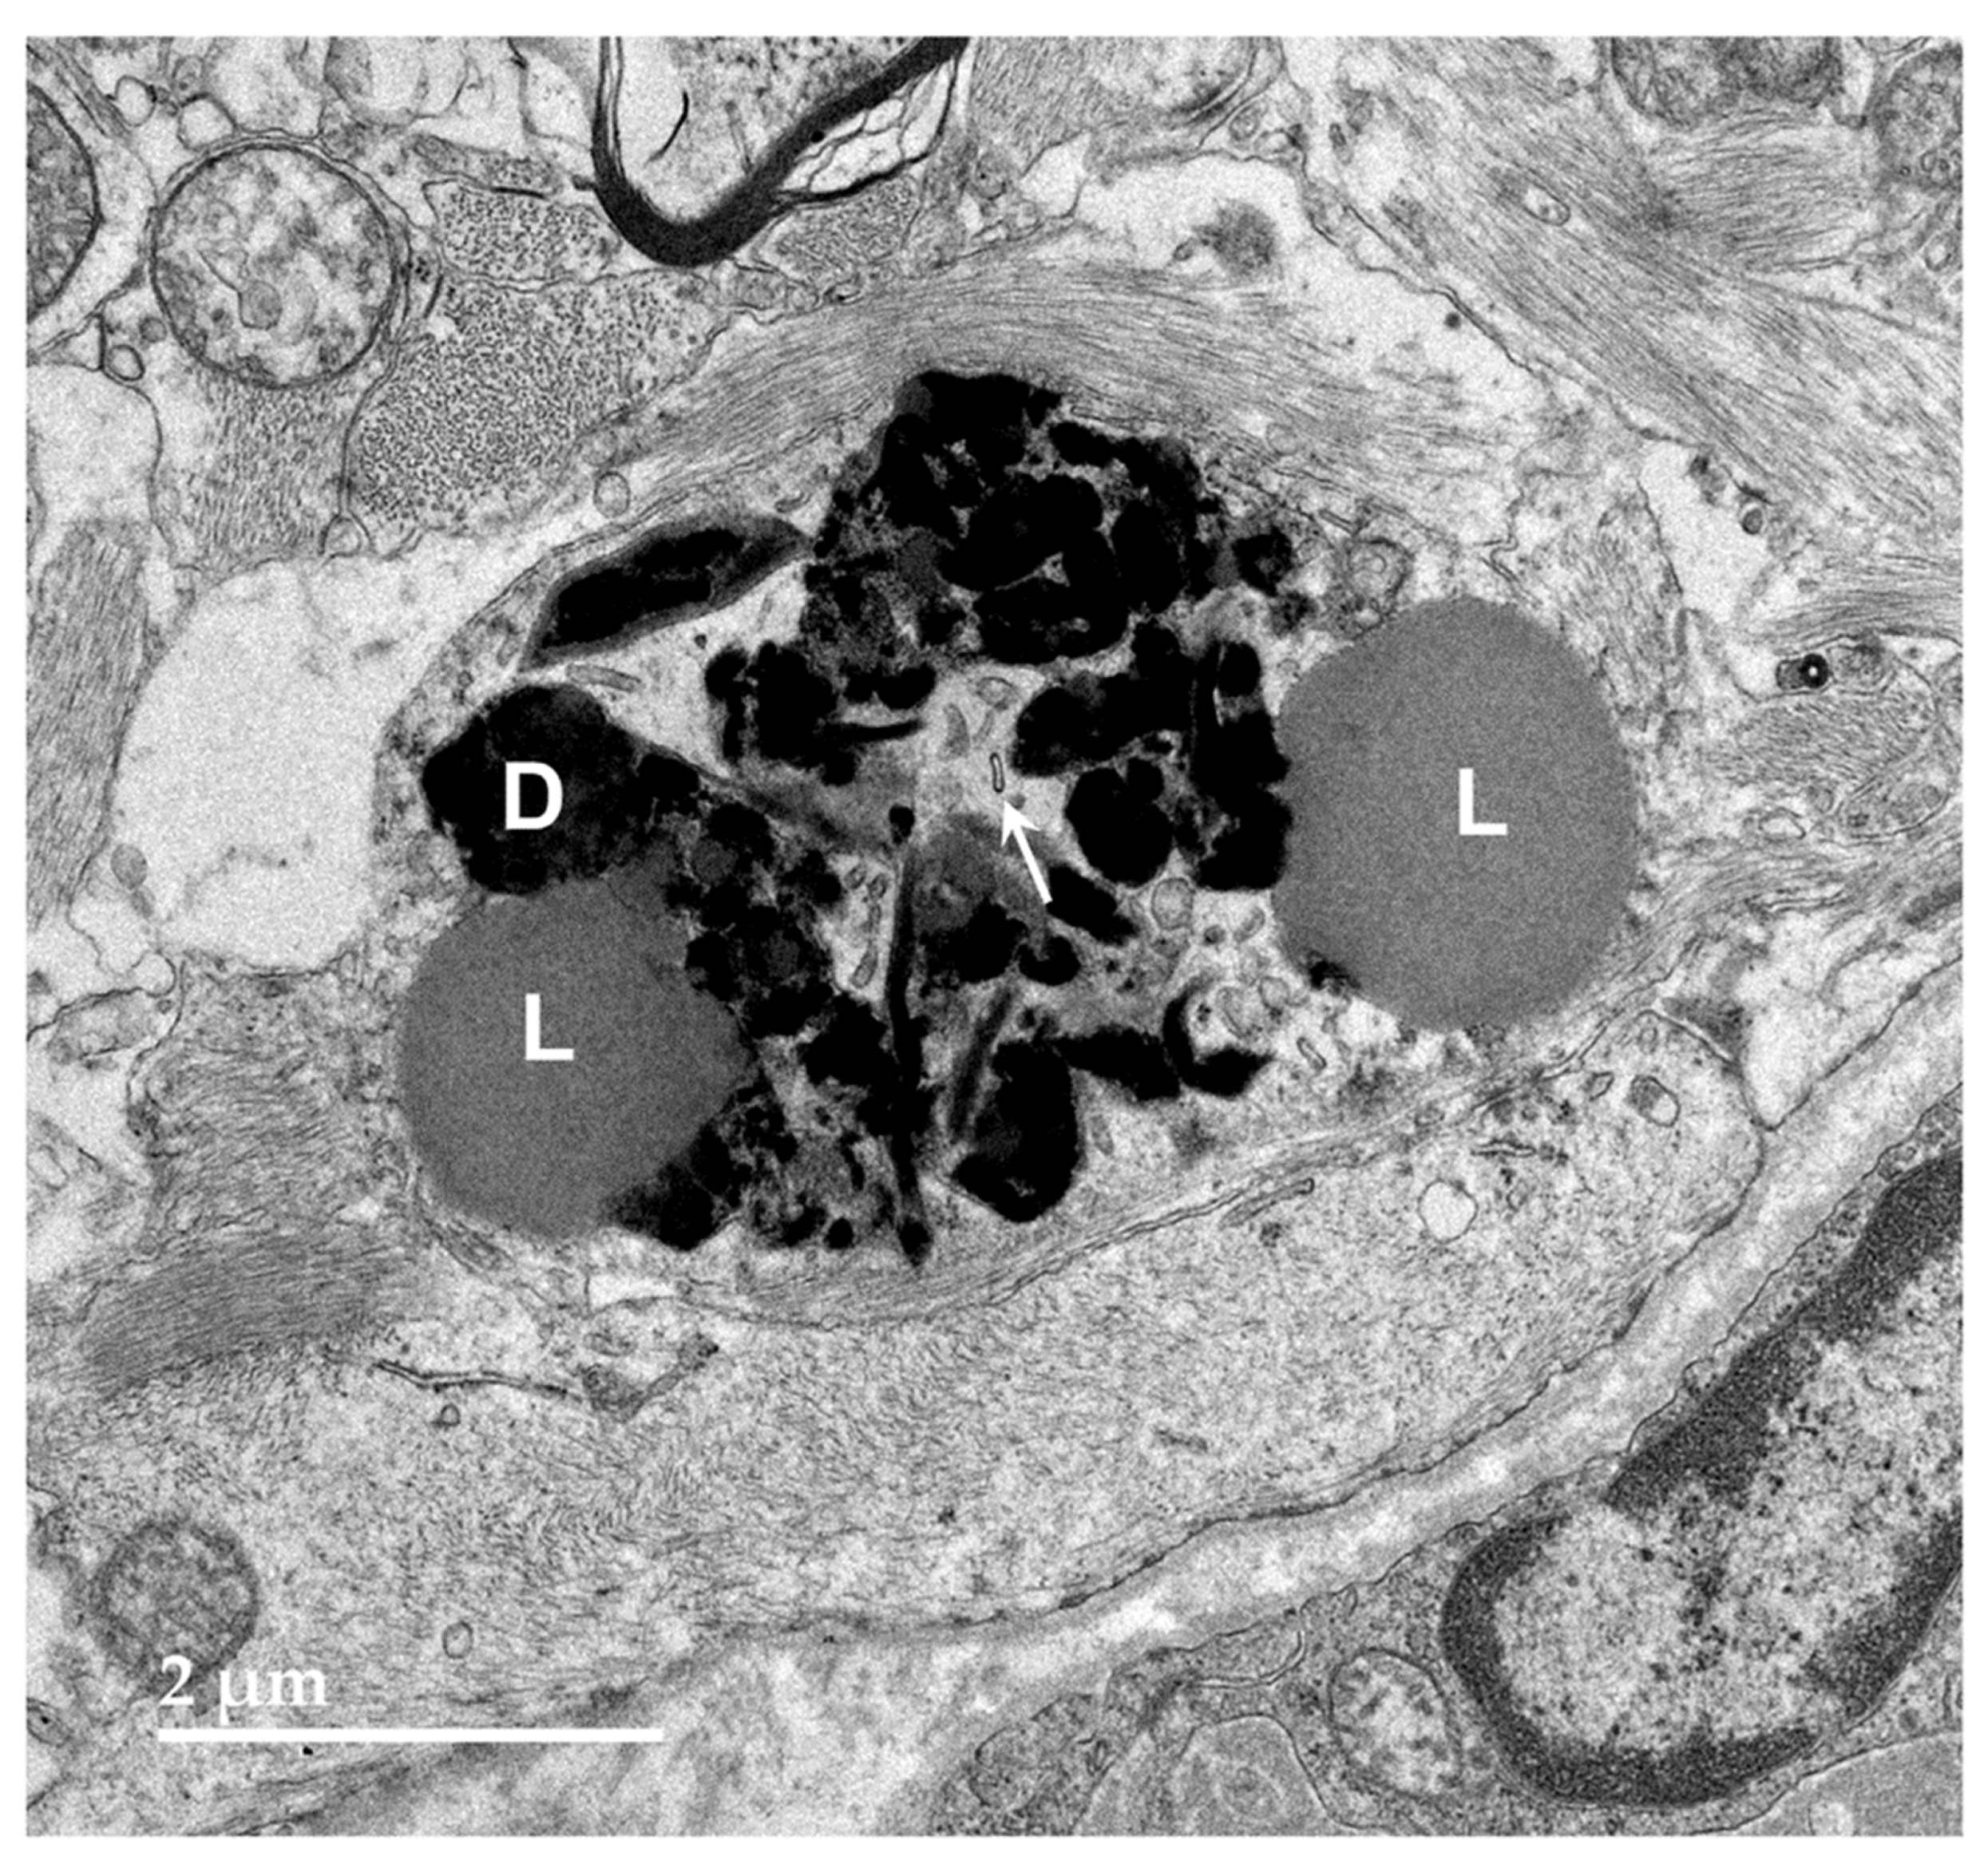

Figure 8. Electron micrograph of an intracellular inclusion in a cell of the cerebral cortical white matter of the proband. The contents of the inclusion body were heterogenous, consisting primarily of lipid-like components (L), aggregates of very electron-dense globular structures (D), and small vesicular structures (arrow).

Figure 9. Electron micrograph of a large cluster of intracellular inclusions in the cerebral cortical white matter of the proband. The contents of the inclusion bodies within the cluster were heterogenous, consisting of lipid-like components (L), aggregates of very electron-dense globular structures (D), and membrane-like components (arrows).

Electron microscopic examination of the cerebral cortex gray matter revealed the presence of membrane-bounded organelles containing mixtures of materials that included granular components of varying electron density, membranous components, and lipid-like inclusions (Figure 4 and Figure 5). Organelles with similar heterogeneous contents were present in the cerebellar cortex gray matter (Figure 6 and Figure 7), in the cerebral cortical and cerebellar white matter tracts (examples from the cerebral cortical white matter shown in Figure 8 and Figure 9), and in the optic nerve (Figure 10). The myelin sheaths of the optic nerve and of the brain white-matter axon tracts contained numerous areas of large abnormal gaps between the layers of myelin (Figure 11 and Figure 15). In the optic nerve, it appeared that some of abnormal myelin had budded off from the axonal sheaths and was taken up into the adjacent cells forming structures that contained whorls of membrane (Figure 12, Figure 13 and Figure 14). In the brain white matter tracts, some of the axons appeared degenerate, with the axoplasm replaced by myelin-derived membrane and membrane fragments that appeared to have collapsed inward into the axon (Figure 16).